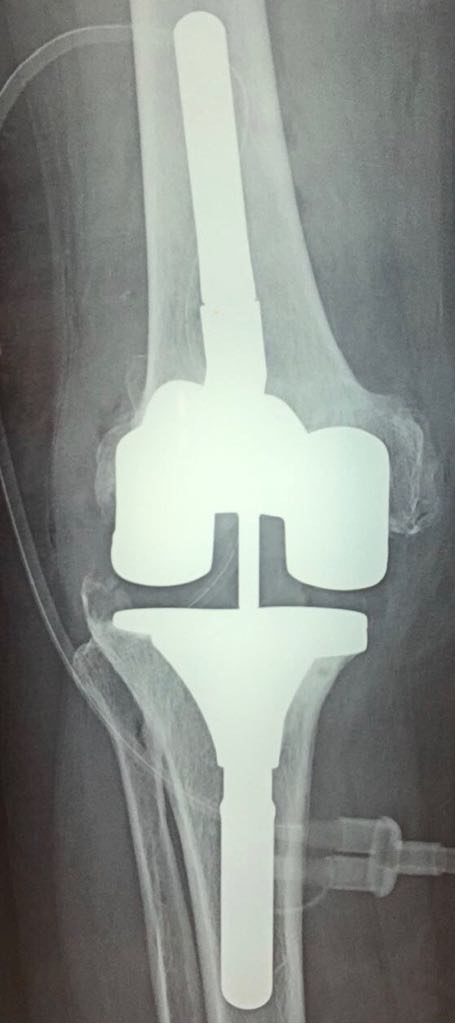

PTG de reprise d’essai (photo per-Operatoire)

PTG de reprise implant définitif cimenté (photo per-operatoire)